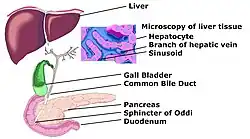

Schematic diagram of biliary system

Schematic diagram of biliary system -